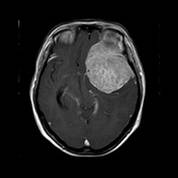

经查体,神经外六科吴杰主任诊断为:左侧蝶骨嵴占位性病变,考虑脑膜瘤可能性大。之后黄女士完善了相关检查,颅脑CT及CTA检查提示:左侧中颅窝底巨大占位病变,其内血管丰富,临近左侧大脑中动脉明显受压向上移位,考虑脑膜瘤;颅脑磁共振提示:左侧前中颅窝底巨大占位性病变,考虑脑膜瘤。介入栓塞提示:肿瘤主要由左侧脑膜中动脉额支、少量由左侧眼动脉脑膜支参与供血。

术前MRI可见左侧额颞巨大占位,增强均匀强化,考虑脑膜瘤